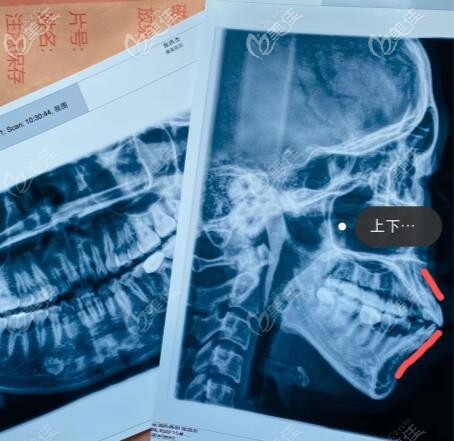

因为矫正失败了,幻想破灭的太快一下子接受不了现实,但我也不死心,就又去了几家业内有名的整形医院面诊,直到遇见武汉亚韩赵贵庆院长后,我才知道自己是骨性嘴凸,不适合做正畸治疗,只有做正颌手术才能改善。

这是我骨性凸嘴做正颌手术一年半,一路看到自己侧脸的变化我真的好开心,下巴内收了7mm,嘴凸问题得到了有效改善,整个面型协调很多,后悔自己没早点去做正颌手术。